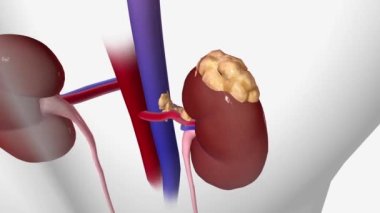

İnsanmikroSağlıkkanİlaçdikkatHastagövdeTedaviHastalıkbiyolojikanserbölümSistemAcıorgAyrıntılarkanaltaşlartüplerTeşhisanatomiBağışMikroskopfizyolojiNanoBöbreklerBöbrekİdrarfiltrasyonTümörmorfolojiiltihabımikroskopidonöriç organlara aitÜrogenitalÜrolojinefrithistolojiÜreböbreküstüDiyalizGlomeruluspiyelonefritnefronÜrologHematoksilenhydronephrosisurolithiasisBenzer İçerikler